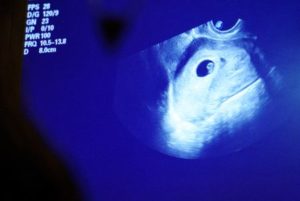

An ultrasound is taken ahead of a surgical abortion as patients receive care at Blue Mountain Clinic in Missoula, Montana, U.S. February 23, 2023. Currently, abortion is legal in Montana based upon a constitutional right to privacy, which was affirmed by the state Supreme Court’s decision in Armstrong v. State in 1999. However, the republican-controlled congress has introduced a number of bills to restrict access to reproductive care – most notably House Bill 721, which seeks to limit dilation and evacuation, the most common procedure for terminating pregnancies after the first trimester. REUTERS/Callaghan O’Hare